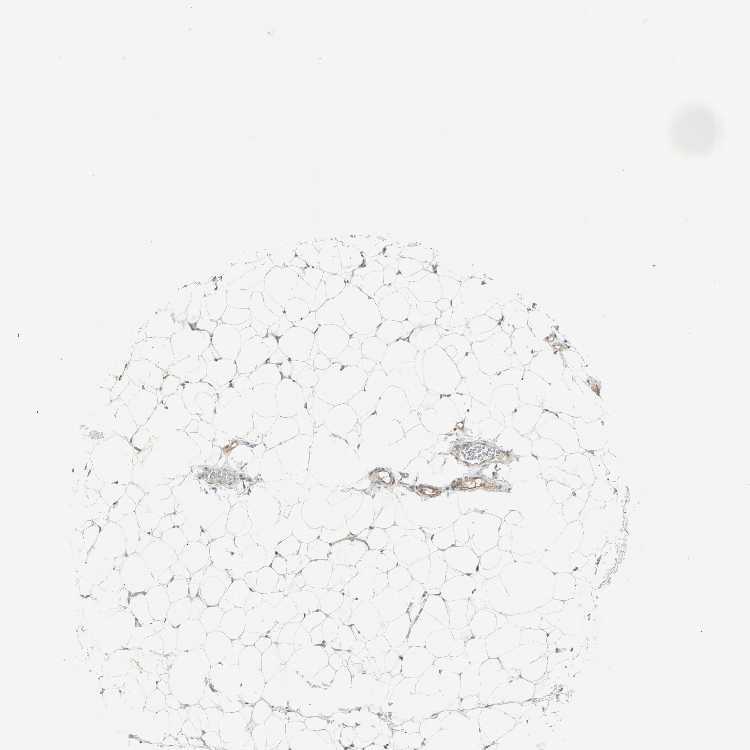

SOFT TISSUE 2 - Antibody stainingi

Antibody staining in the annotated cell types in the current human tissue is reported as not detected, low, medium, or high, based on conventional immunohistochemistry profiling in selected tissues. This score is based on the combination of the staining intensity and fraction of stained cells.

Each image is clickable and will lead to virtual microscopy that enables deeper exploration of all samples and also displays staining intensity scores, fraction scores and subcellular localization as well as patient and tissue information for each sample.

Antibody HPA007267

Fibroblasts Low

Peripheral nerve Low